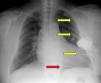

Doente do sexo masculino, de 60 anos, com antecedentes de hipertensão arterial e enfarte agudo do miocárdio (EAM) anterior extenso em 1997. Seis anos após o EAM e na sequência de episódio sincopal, foi documentada a presença de taquicardia ventricular (TV) monofórmica com intervalo R-R de 320 milisegundos (ms). O ecocardiograma revelou ventrículo esquerdo dilatado, de paredes não espessadas com deficiente função sistólica global (fração de ejeção de 35%) e presença de discinésia apical, acinesia dos segmentos medianos e hipocinésia dos segmentos basais da parede anterior e septo anterior. No cateterismo cardíaco verificou-se oclusão crónica proximal da descendente anterior e estenose de 25% do segmento proximal da circunflexa. Implantou CDI Guidant® MINI II para prevenção secundária. Durante a implantação do CDI, constataram-se limiares de desfibrilhação elevados, o que levou à necessidade de implantação de um elétrodo de choque adicional subcutâneo array para alargamento da área de aplicação do choque (Figuras 1–3).

Em 2002, foi submetido, eletivamente, a substituição de gerador por exaustão com implantação de CDI CPI Prizm 2 VR, tendo efetuado testes de desfibrilhação com sucesso com choque de 20 Joules.